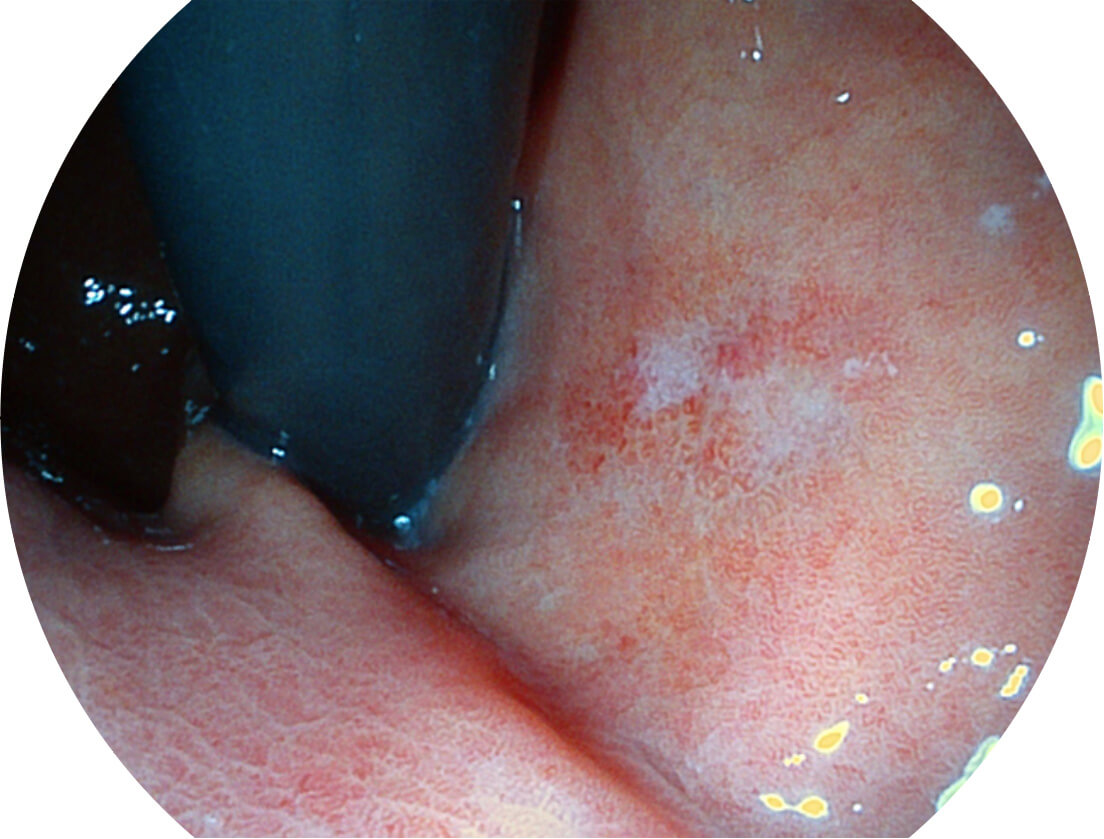

Spectral Focused lmaging, SFI

图像具有高亮度、高黏膜血管颜色对比度的特点,且不改变粘液、食物残渣、粪便的基本颜色,可在中远景下进行观察,助力消化道早期疾病的诊断。

SFI图像

采用光路合束技术,光谱自由度高,实现了更丰富的照明模式,染色模式SFI及VIST,从远景到近景,助力消化道早期疾病诊断。